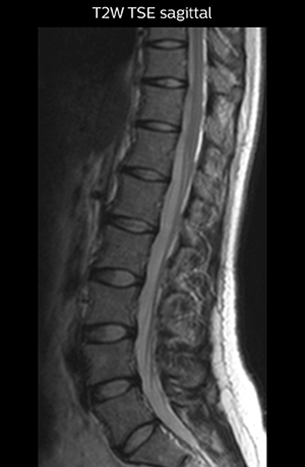

“For example, in sagittal images, when the presence of fat is observed in the intervertebral foramen, it suggests that there is a margin around the nerve. Similarly, the absence of fat indicates that the nerve is being compressed. So, we used to deduce nerve compression indirectly. With NerveVIEW, however, we can observe the condition of the nerves directly, regardless of the presence or absence of fat. We always prefer such direct observation of anatomy over having to make an inference about it.”

“Although symptoms of typical disc herniation and atypical hernia are very similar, the actual site of herniation is different. It is therefore important to characterize the nerve’s condition both inside and outside of the intervertebral foramina. “Conversely, if we see no abnormality in NerveVIEW, we can assume at least that there is no severe condition that requires surgery. Like this, it can help us avoid unnecessary surgery. NerveVIEW can have a tremendous impact in this way.”

“The intra-luminal signal of veins, especially around the intervertebral space, can be suppressed well with NerveVIEW. As a result, we can easily observe the detailed nerve structure around the posterior ganglion,” he says. “This is why we use 3D NerveVIEW for intraforaminal stenosis and extraforaminal stenosis/herniation (lateral disc herniation). On the other hand, if herniation is suspected to exist inside the dorsal root ganglion (DRG), balanced TFE or ProSet-FFE is applied. NerveVIEW is not suitable for evaluating the median type of herniation.” The SE-EPI DWI-based method for MR neurography works well for large FOV exams like whole-body MRI, but focal examination of nerves is often limited by the attainable spatial resolution (both inplane and slice direction) and geometric distortion. “3D NerveVIEW achieves higher in-plane resolution – close to our other routine spine sequences – and the source images can be used instead of adding a fat-suppressed T2-weighted sequence,” Tanji says.